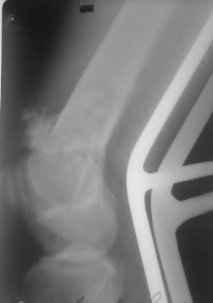

01.12.09г. оперировал больного с подобной травмой в ЦРБ на 4-е сутки после ДТП. Перелом открытый - рана находилась медиально чуть выше надколенника длиной примерно 3-4 см. До этого при поступлении было выполнено ПХО раны и скелетное вытяжение. На момент операции рана без признаков воспаления, состояние больного удовлетворительное.На первичных снимках перелом А3. На операции оказалось С3. Перелом фиксирован мыщелковой пластиной. Для репозиции понадобился медиальный доступ. Медиальный блок дополнен костно-губчатым аутотрансплантатом. На сегодняшний день раны заживают первично, швы еще не сняты, температура тела нормальная, отек бедра значительно уменьшился, имеется анемия средней степени, проводится ЛФК. Фото досылаю

Чем остеосинтез аппаратом в этом конкретном случае был бы предпочтительнее - и менее инвазивно, и пластику бы не надо было делать, и ось можно было бы лучше контролировать, включая послеоперационный период. А сейчас варусный коллапс градусов 15, и для исправления оси потребуется отдельная операция...

Снимки лучше бы делать на большем протяжении.